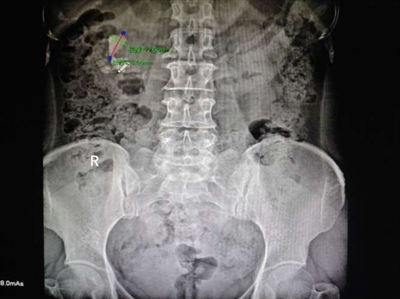

据了解,咸宁辛勤结石医院为患者吴女士成功施行输尿管软镜联合钬激光碎石取石术。术后患者自觉无创轻松,2小时即可正常活动,术后各项检查指标良好,B超、X线拍片显示,肾盂内3.5×2.2cm结石完全粉碎,短期内绝大部分碎砂排出体外,从手术到出院仅用5天时间。